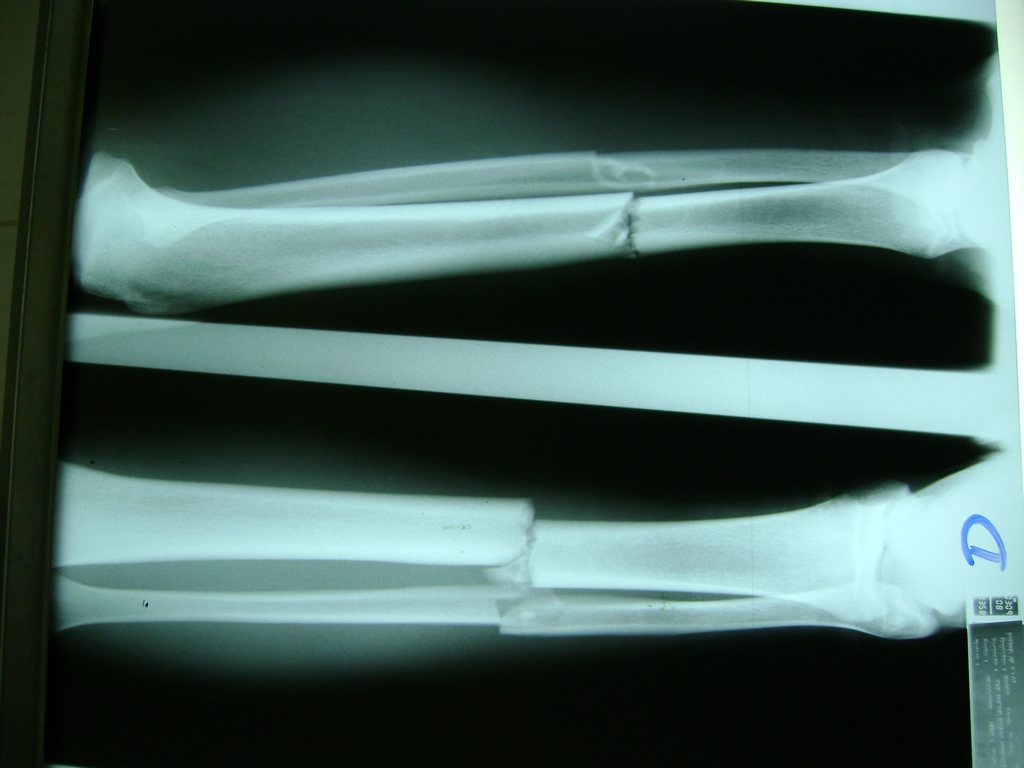

Cirugía de Tibia y Peroné

Aunque cada uno de estos huesos puede fracturarse por separado, normalmente la rotura es una lesión que se produce de forma conjunta

La mayor parte de las roturas implican a la parte proximal del hueso (parte del hueso próximo a la rodilla) o a la parte distal (parte del hueso cerca del tobillo).

Debido a la fina cobertura de piel que recubre la tibia y el peroné, las fracturas generalmente son abiertas, es decir, el hueso roto rasga la piel, atravesándola. Las fracturas de tibia y peroné generalmente se producen por un fuerte impacto o torsión.